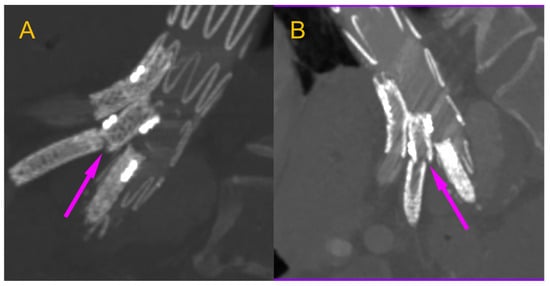

We present the case of an 82-year-old male patient who appeared in the emergency department due to progressive weakness and abdominal pain (2024). Due to a drop in blood pressure to 80/40 mmHg, a continuous infusion of norepinephrine was initiated. The hemoglobin level was approximately 5.1 g/dL. His medical history included generalized atherosclerosis, renal failure, and a thoracoabdominal aortic aneurysm (TAAA) treated with endovascular aneurysm repair (EVAR) using stent-graft implantation 4 years earlier (2020). At that time, the angio-CT scan revealed an aneurysm starting just below the celiac trunk, extending to the superior mesenteric artery (SMA) and both renal arteries (RAs). The maximum diameter of the aortic aneurysm was 51 mm; however, the left common iliac artery measured 41 mm in diameter, an indication for thoracoabdominal stent graft implantation. The aortic aneurysm itself was completely free of mural thrombus. The patient had also experienced a heart attack 16 years earlier and a transient ischemic attack (TIA) 2 years earlier. Following the stent graft implantation, he underwent multiple successful interventions to address endoleaks. One year after implantation, endovascular treatment with embolization coils was performed to eliminate leakage from the lumbar artery (LA) (2021). Three years post-implantation, he was admitted to address leakage from the inferior mesenteric artery (IMA) using embolization coils as well (Figure 1) (2023). In 2024, an X-ray and CT scan revealed a rupture in a branch of the stent graft located in the SMA in its middle part, along with an enlarged aneurysm sac (74 mm) due to the fracture and leakage (Figure 2, Figure 3, Figure 4 and Figure 5). The angio-CT scan did not reveal any contrast extravasation beyond the vessel wall. However, significant contrast leakage was visible in the area of the visceral arteries within the aneurysm sac. The implanted device was the Zenith t-Branch Thoracoabdominal Endovascular Graft, and the ruptured branch was identified as the Bentley BeGraft (Bentley InnoMed GmbH, Hechingen, Germany). Urgent surgical intervention was performed. Intraoperative angiography (IA) showed a breach in the continuity of the BeGraft material within the SMA, with contrast leakage into the aneurysm sac (Figure 6 and Figure 7). To address the leakage and restore the continuity of the SMA branch, an additional BeGraft Plus 8 × 57 mm was implanted into the damaged branch. Subsequent IA and control CT scans confirmed the elimination of leakage, restoration of stent graft continuity, and revascularization of the SMA (Figure 8, Figure 9 and Figure 10). The surgery was completed without complications, and the patient was discharged home in good general condition. The patient returned for follow-up 3 weeks after the last intervention. An angio-CT examination was performed, revealing no enlargement of the aneurysm sac (74 mm), confirming the elimination of the endoleak, and demonstrating successful revascularization of the SMA. Ongoing follow-up will be continued.

Figure 2. Thoracoabdominal aortic aneurysm with a visible T-Branch stent graft inside. The aneurysm diameter is marked with a green line. Pre-interventional Angio-CT scan performed at the time of the patient’s admission. Axial projection, arterial phase.